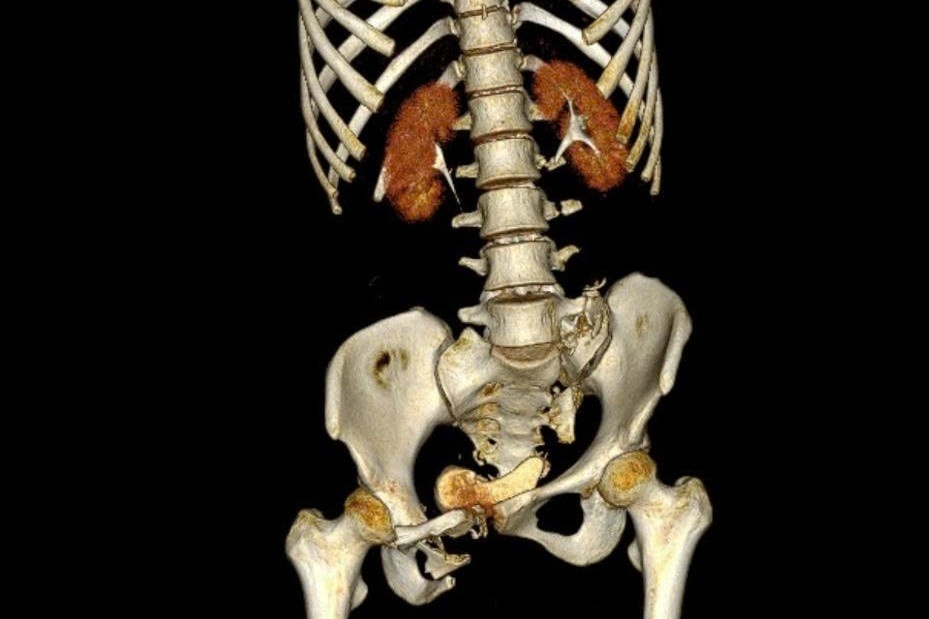

Ảnh chụp CT dựng hình 3D cho thấy bệnh nhân bị dập phổi phải, vỡ bàng quang và buồng trứng phải gây xuất huyết ổ bụng, gãy gai ngang các đốt sống từ L2 đến L5, kèm gãy phức tạp khung chậu kiểu “gió thổi”.